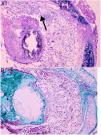

ResultsControl group is representative of the typical BO lesionAs stated in Material and Methods, we used a heterotopic rat transplantation animal model for reproducing the BO lesion. After 21 days, allografts were retrieved and analyzed (H–E staining). All 5 animals in the control group demonstrated absence of epithelium and dense collagen tissue with no inflammatory infiltrate occupying the lumen of the allograft (Fig. 2). These findings are consistent with previously published histological patterns using this model,11,14 such as loss of epithelium and base membrane, and fibrous obliteration of the lumen.

BO typical lesion observed in control group (CG) (25×, H–E). The tissue located in the lumen of the allograft is mainly formed by scar tissue (collagen and fibroblastic cells) (black arrows). (A) Overview of a section of the tracheal segment. (B) Detail of the scar tissue (collagen and fibroblastic cells).

Histological qualitative analysis showed numerous large neovessels in a very loose fibrous tissue matrix with no inflammatory infiltrate (Fig. 3). Trichromic staining showed collagen deposition in both cartilaginous and membranous walls of the allograft, and a loose collagenous net inside the lumen. These findings were found in all groups.

(A) Histological findings in groups than received BMSC. These findings consist in a large number of neovessels in a very loose collagen bed (25×, H–E). The arrow is pointing to a one of the neovessels. (B) Next section of the same histologic sample showing the loose collagen tissue (green color) with trichrome staining (25×).